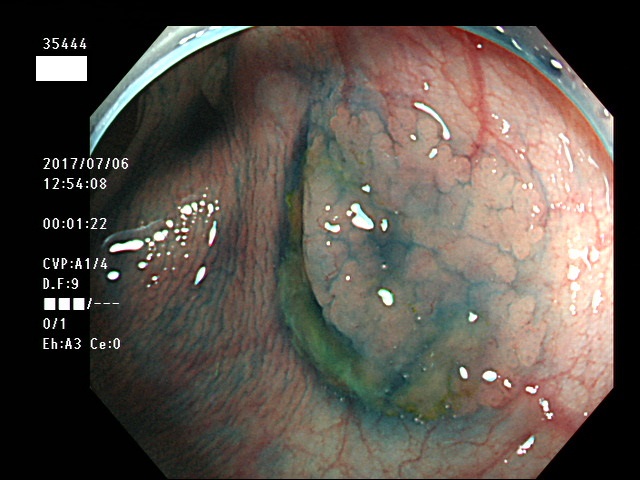

上記100名より抽出した平坦・陥凹型腺腫・SSAP(=癌化の危険が高いが見落としやすい病変)の内視鏡写真

35403 35404 35405 35409 35410 35412 35413 35414 35416 35417 35418 35419 35420 35421 35426 35429 35430 35433 35434 35435 35438 35439 35440 35444 35445 35447 35449 35450 35451 35452 35453 35454 35458 35460 35463 35464 35466 35468 35469 35470 35472 35473 35478 35479 35481 35483 35485 35489 35490 35491 35492 35493 35498 ・・・・・の54名